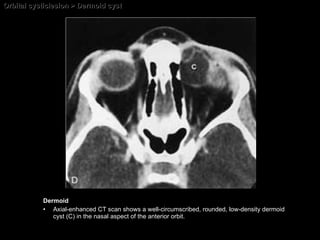

Dermoid cyst  Choristoma  = a focus of tissue histologically normal for an organ or part of an organ at a site other than the site at which it is located. Dermoid or epidermoid cyst :::: A dermoid or epidermoid cyst is a choristoma.  M/C orbital tumors of childhood.  Most frequently  found in favor the upper portion of the orbit (temporal > nasal). The tumor is congenital but may not be noted at birth.  Many become evident only in the 2nd decade.

CT AND MR IMAGING FEATURES Intensity of adipose tissue Density of adipose tissue Dermolipoma HypoSI on T1WI and hyperSI on T2WI Fatty tissue Minimal enh of capsule may be present Associated orbital inflammatory changes, when cyst is ruptured Non-enh mass with or without bone erosion Calcification, if present, is a characteristic feature fat, if present, is characteristic  Scalloping with sclerosis of the adjacent bone may be present Minimal enh of the capsule may be present Dermoid cyst HypoSI on T1WI and hyperSI on T2WI Minimal enh of capsule may be present Associated orbital inflammatory changes, when cyst is ruptured Non-enh mass with or without bone erosion No calcification Scalloping with sclerosis of the adjacent bone may be present Minimal enh of the capsule may be present Epidermoid cyst MRI CT

Orbital cysticlesion > Dermoid cyst Dermoid Axial-enhanced CT scan shows a well-circumscribed, rounded, low-density dermoid cyst (C) in the nasal aspect of the anterior orbit.